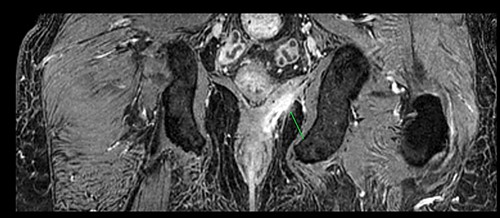

A 61-year-old diabetic patient was admitted from emergency department with septic signs; fever of 39°C, white blood cell count of 20.000/μl, C-reactive protein levels of 156 mg/l and blood glucose levels of 280 mg/dl. For the past 10 days, the patient has noted malodorous anorectal pus discharge, as well as anorectal and suprapubic pain. During macroscopic examination of the perineum, a left-sided abscess in the ischiorectal fossa was identified, with an opening lateral to the sphincteric anal system draining pus. Subsequent digital rectal examination of the anorectal canal could not be completed due to pain, but the initial effort revealed large amounts of pus discharged from anorectal canal. CT and MRI demonstrated an abscess situated in the left ischiorectal fossa and a large supralevator abscess extending cephalad in the extraperitoneal space with a long fistulous tract containing liquid (pus) and gas bubbles, up to the suprapubic area, where erythema with an undulating pus collection below the skin was noted; laterally the pus collection extended up to the left ilio-femoral vessel canal. CT (Fig. 1) and MRI (Fig. 2) were conclusive for the above entity, aptly demonstrating the presence of the two abscess cavities. Proctoscopy under general anesthesia revealed a protruding extra-rectal mass in the left lateral and inferior segment of the rectal ampulla. Finger pressure at this point was accompanied with pus exit from the posterior dentate line of the anal canal at 6 o’clock, through an opening of 1–2 mm in size. Surgery was addressed in three main locations of the pus collection with goal to drain completely the pus; the abscess of the left ischiorectal fossa was drained with enlargement of the external opening of fistula; after curettage, debridement and washing of abscess cavity, a probe was used to detect the internal opening exactly at the posterior dentate line at 6 o’clock. The fistula was characterized as full trans-sphincteric with an extra-sphincteric component in the ischiorectal fossa leading up to the skin. A non-cutting vessel loop drainage seton was then placed. The supralevator abscess was then easily drained from the opening in the posterior dentate line by finger pressure in the left rectal ampulla. A probe following the route of the internal opening upwards to supralevator space led to pus evacuation, allowing this space to be thoroughly washed with water saline solution, using a syringe with a vein catheter. Finally, the suprapubic area was drained with a small stab incision, followed by washing with normal saline. There was a prompt recovery postoperatively, tight control of blood glucose levels, whereas a CT performed 7 days postoperatively (Fig. 3), demonstrated an empty supralevator space with a fistulous tract still present, albeit with significant regression of inflammatory changes.

Postoperative CT of the lower pelvis, demonstrating a collapsed left supralevator space and superiorly expanding fistulous tract.